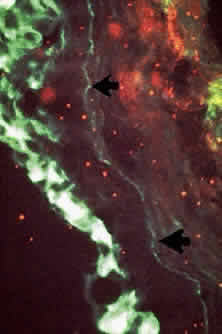

Conjunctival biopsies taken from patients with CP demonstrate immunoglobulins and complement bound to the basement membrane (Fig. 9) 24,37–43 One targeted basement membrane component may be laminin.44 The destruction of laminin, which normally binds basal epithelium to its basement membrane, leads to blister formation.45 An animal model of subepithelial blistering diseases has been developed using antilaminin antibodies in neonatal mice.46 Further damage causes fragmentation of the basement membrane and subsequent repair with aberrant forms of basement membrane collagen.47 Immunoglobulin deposition on the conjunctival basement membrane also may be found in other diseases.24,38,43,48

In CP, antibodies may be directed against specific T-cell antigens expressed in the conjunctival epithelium and its basement membrane (Fig. 10).38,39,43,50 In addition, circulating antibodies that bind to the conjunctival and corneal epithelium have been demonstrated.38,39 Studies showing the presence of transforming growth factor-beta 1 and 3, IL-2, and b-fibroblast growth factor suggest that these cytokines play a role in fibrosis.51,52